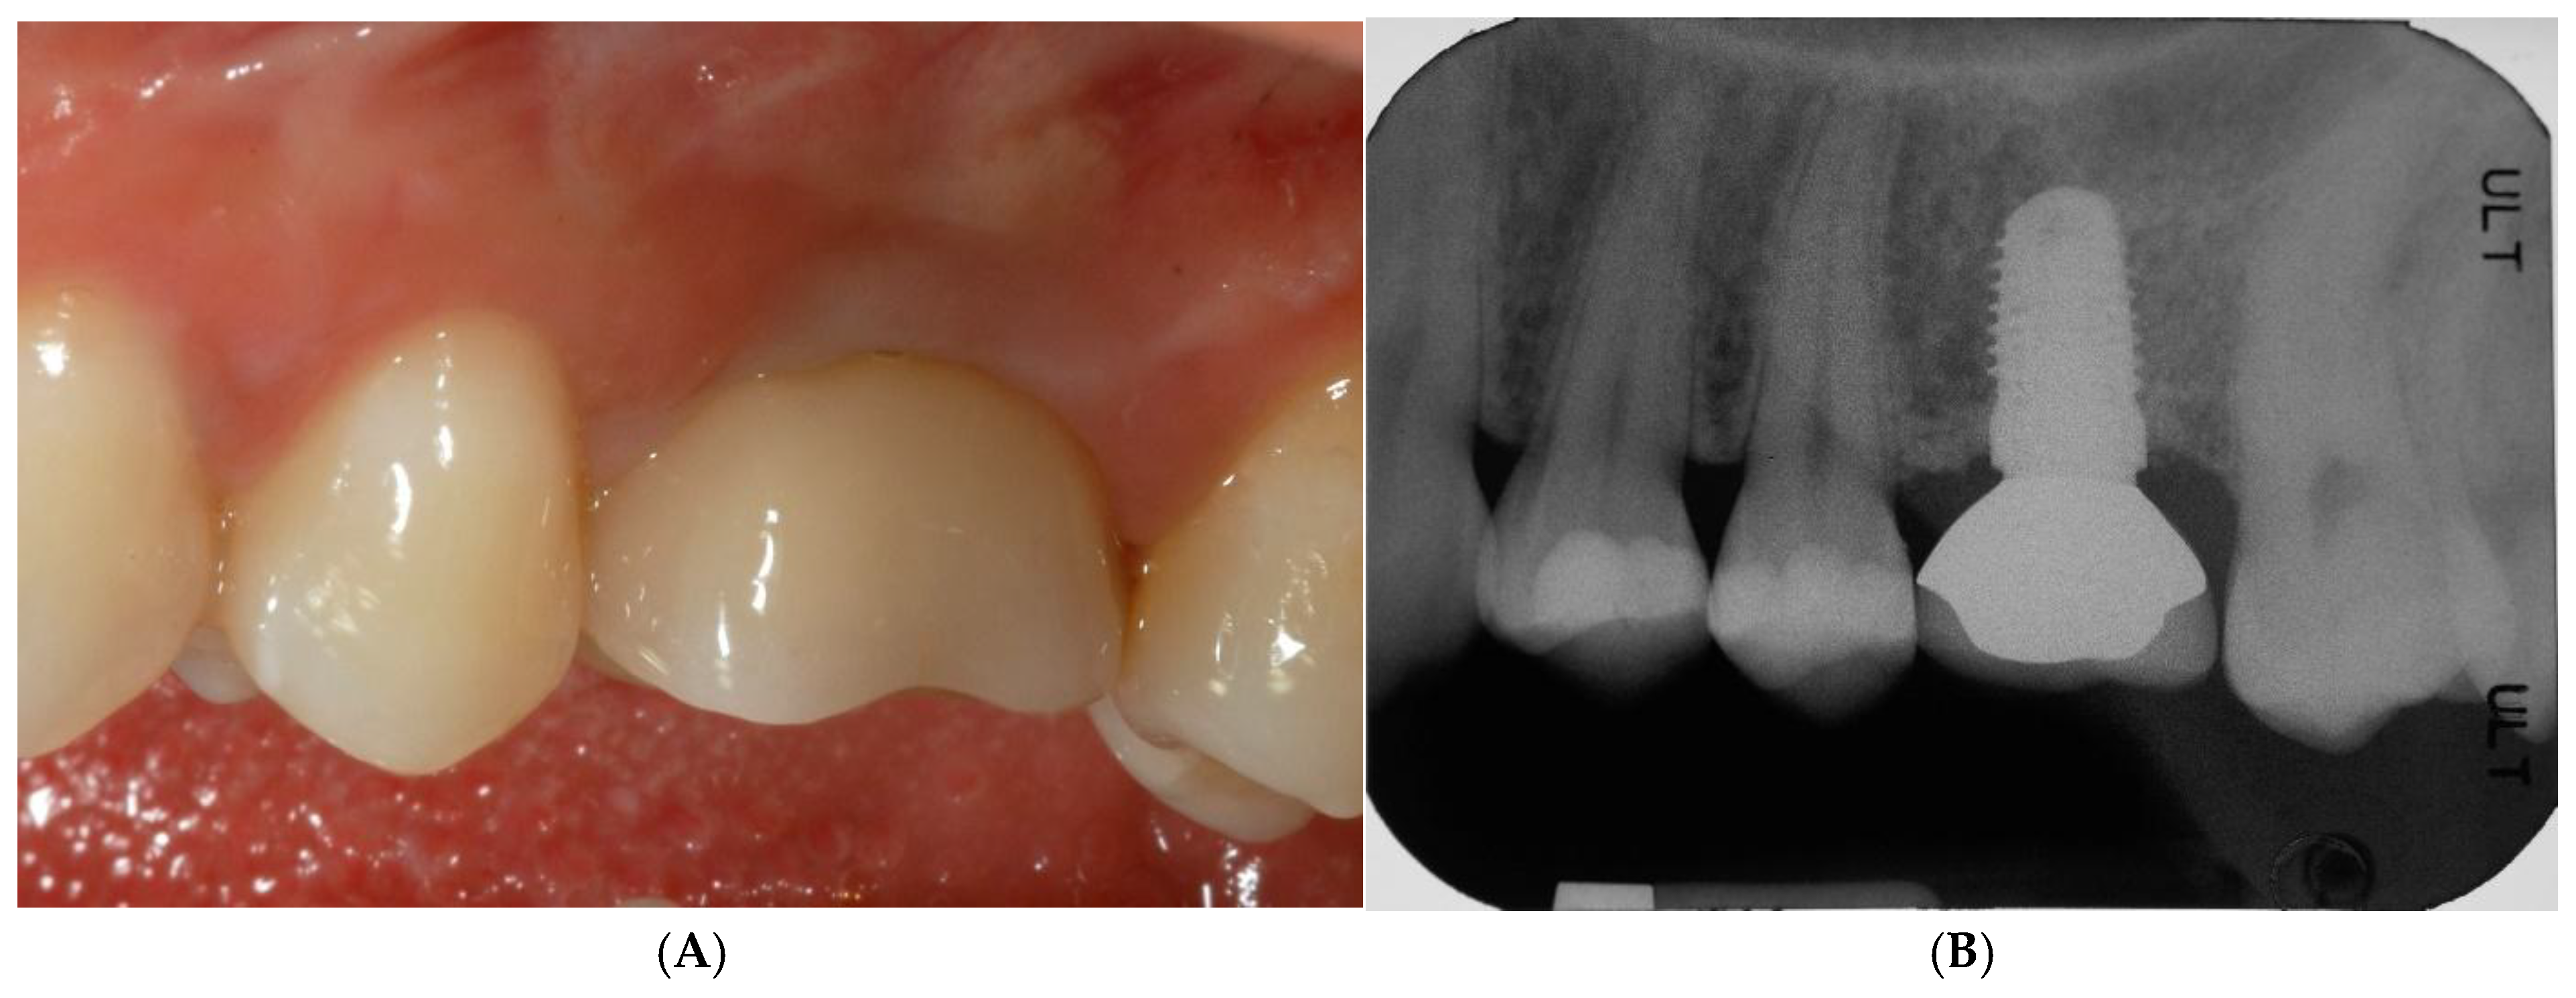

Treatment options were discussed, and the patient signed a consent form for the tooth extraction and the subsequent augmentation procedure, to be scheduled as a staged approach for implant site development. Four months after the tooth extraction, soft tissue healing reached a proper maturation (Figure 2A,B), and a new CT was requested to evaluate the wound healing and bone availability for implant therapy. The CT scans revealed a horizontal ridge defect (Figure 2C,D–F) that required correction with a staged GBR procedure.

Figure 2.

Soft tissue healing four months after tooth extraction (A,B). New CT was requested to evaluate wound healing and current bone availability for implant therapy. CT scans revealed horizontal ridge defect (C–F) that had to be corrected with a regenerative procedure.